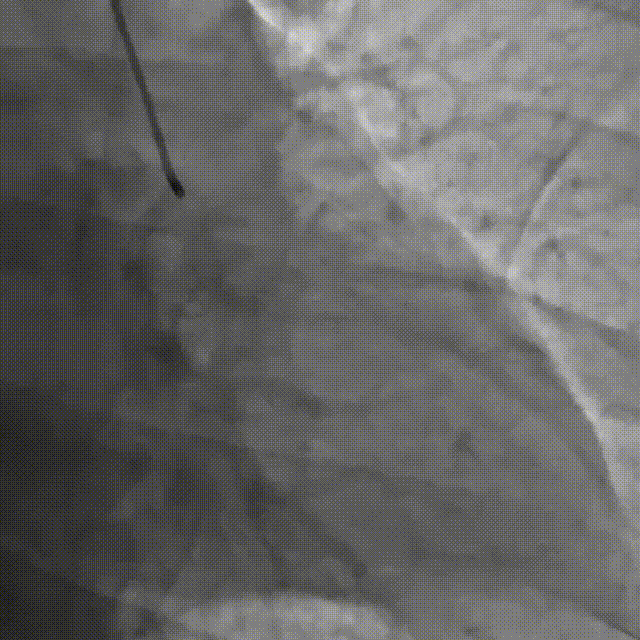

直接尝试逆向,RCA中段3.0*10切割后,使用Finecross150+SUOH03通过心外膜逆向进入LAD,FC轻松跟进。

使用P200导丝攻击远端纤维帽前进困难,更换G3进入LAD近段内膜下,直接使用Telescope™导引延长导管辅助下AGT技术,r-CART后G3顺利进入Telescope™导引延长导管。